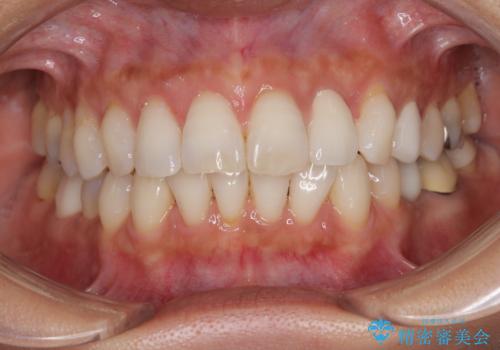

- 目立つ銀歯やむし歯、前歯のデコボコを気にして来院された患者様です。

デコボコはある程度改善できれば良いとのことでしたので、インビザラインの廉価版を用いて矯正治療を行うこととしました。

飛行機での通院であり、更にはご家族がの都合で海外に滞在されることも多いため、中等度の歯列不正に対応可能なインビザライン・モデレートパッケージを使用することとしました。

むし歯治療は、症状のある歯を矯正治療前に処置し、概ね歯列が整ったところで残りのは全て処置し、最後にインビザラインで歯列を仕上げることで、無駄なく治療を進めて行くこととしました。

しっかりと装着時間を守ってくださり、来院のタイミングに合わせてインビザラインの装着期間を調整するなど、協力いただいたおかけで、1年半の期間で全てを終えることができました。